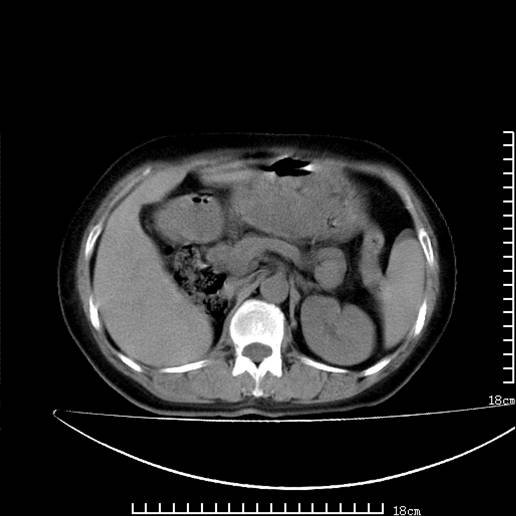

以下是引用pujunzhi在2008-5-30 15:31:00的发言:[br]异位肾—盆腔肾。当看到肾窝无肾脏时,要想到孤立肾和异位肾,异位肾最常见是盆腔肾,偶见胸腔,易误认为肺占位,只要想到就不会漏诊。建议增强扫描。